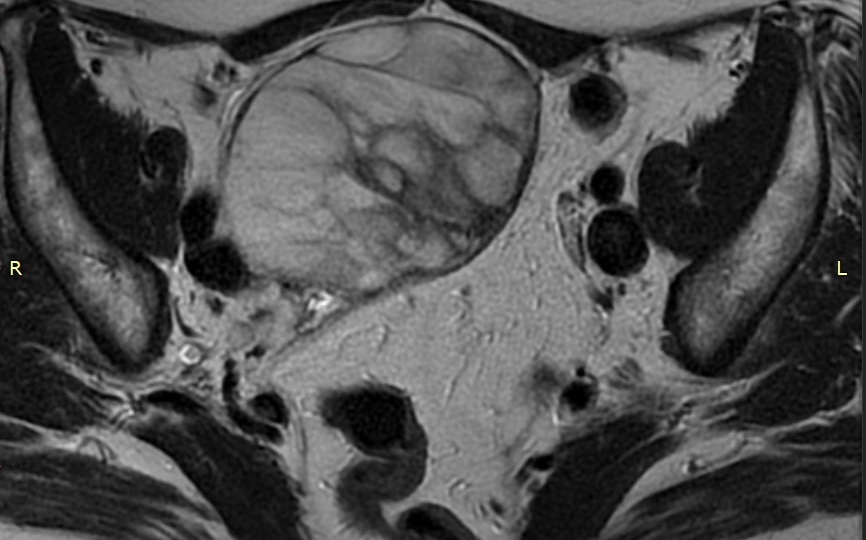

Кисты яичников

Киста яичника представляет собой заполненное жидкостью образование, которое развивается в яичнике и может быть разных размеров и структуры. Это довольно распространённое явление у женщин, особенно в репродуктивном возрасте. Образования яичников являются четвертой по распространенности причиной госпитализации в гинекологические стационары в мире. Кистой яичника в обиходе принято называть любое образование в яичнике кроме злокачественного (рака). Однако разновидностей “кист”, то есть их гистологических типов, существует весьма большое количество. Вместе с тем, доподлинно определить по данным осмотра, УЗИ или МРТ, какой именно вид кисты имеет та или иная пациентка, удается не всегда. В данной статье мы постараемся составить общее представление о методах диагностики и подходах к лечению именно при доброкачественных образованиях яичников. Кисты в яичниках бывают разные и их вид будет напрямую связан с причиной их развития [1]. Принципиально такие образования могут быть функциональными или п